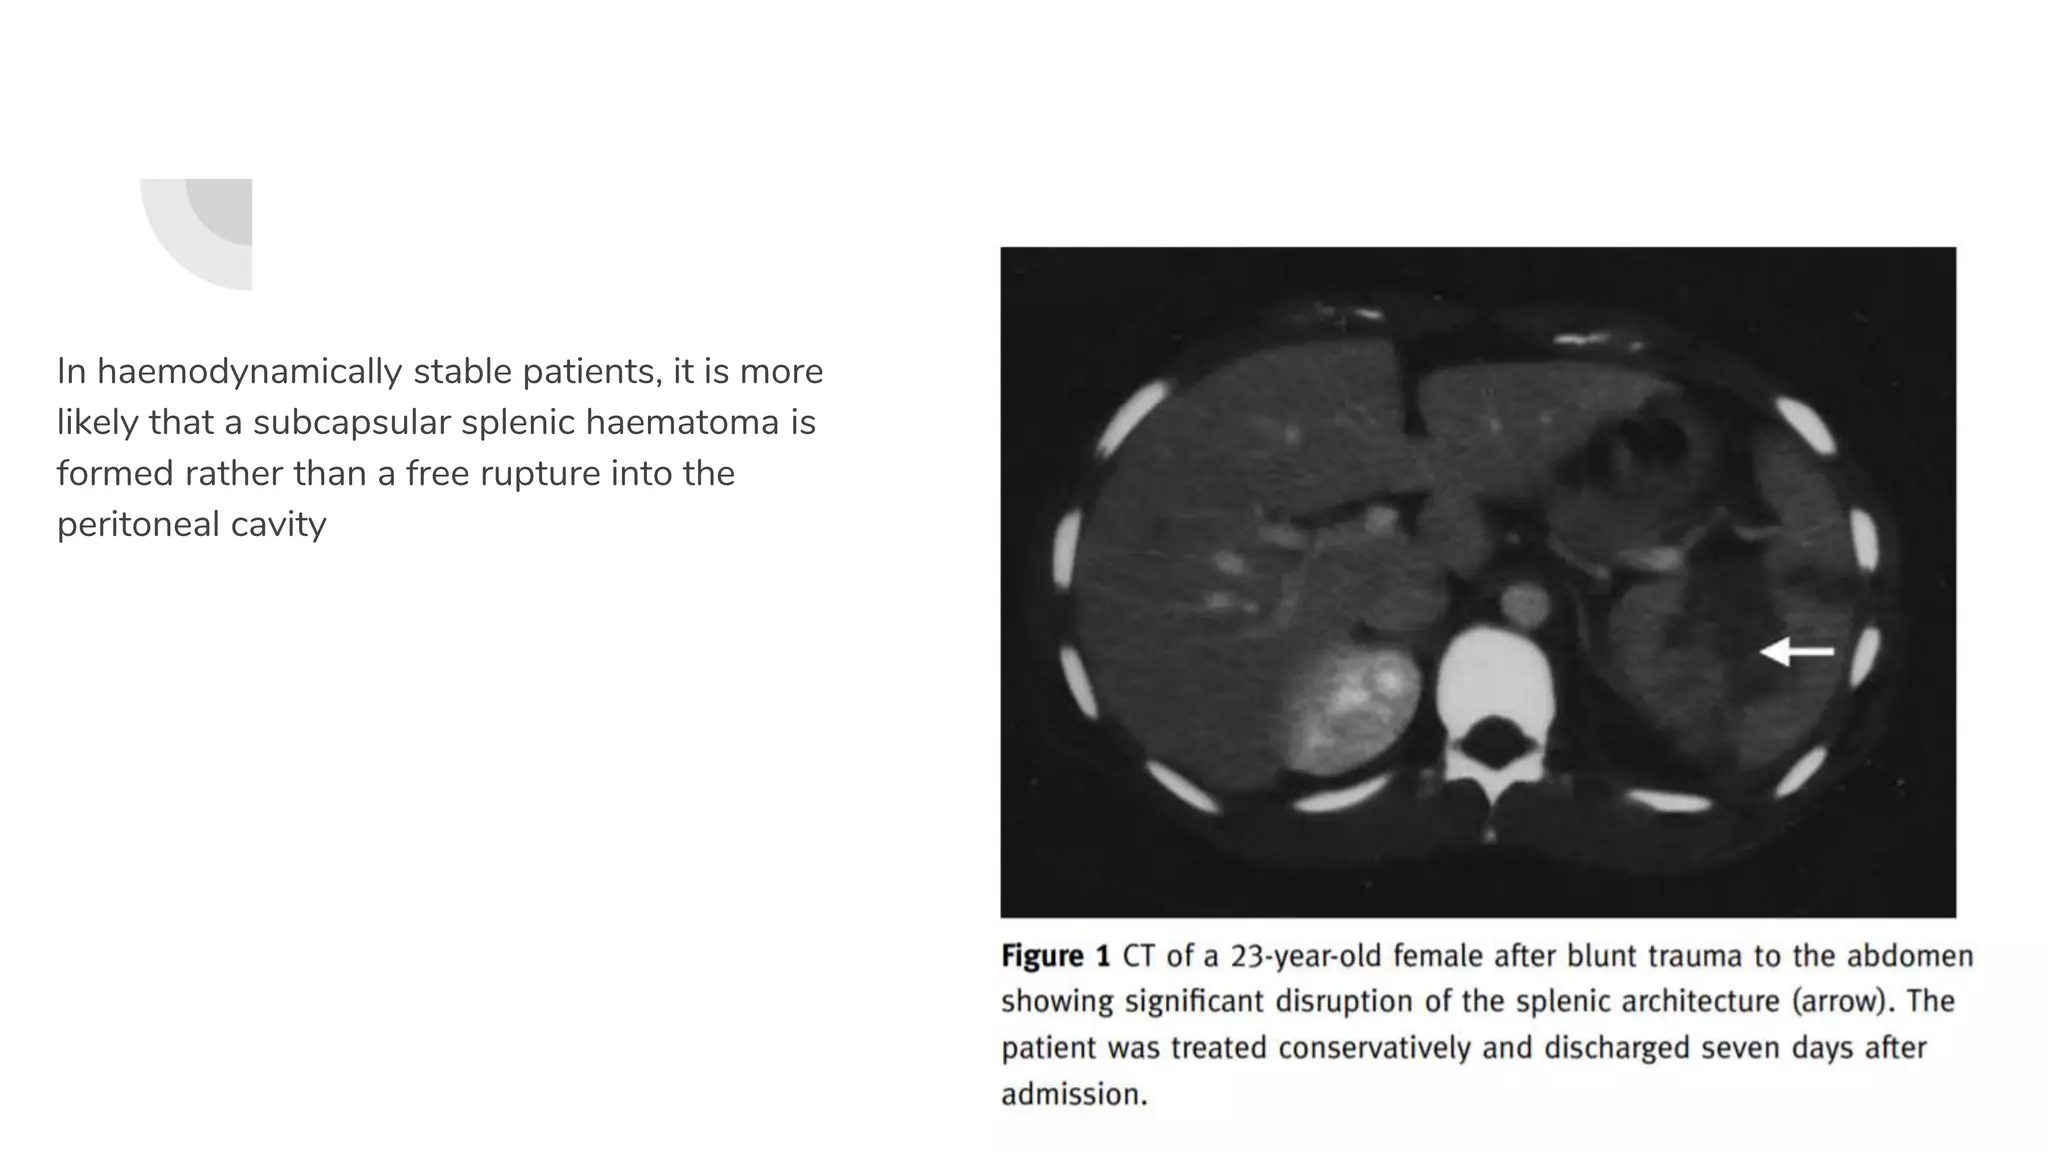

In haemodynamically stable patients, it is more

likely that a subcapsular splenic haematoma is

formed rather than a free rupture into the

peritoneal cavity